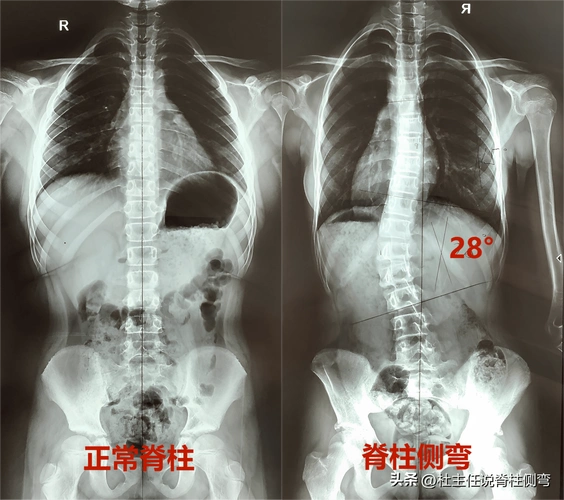

当脊柱侧凸的角度大于10度,即可诊断脊柱侧凸.